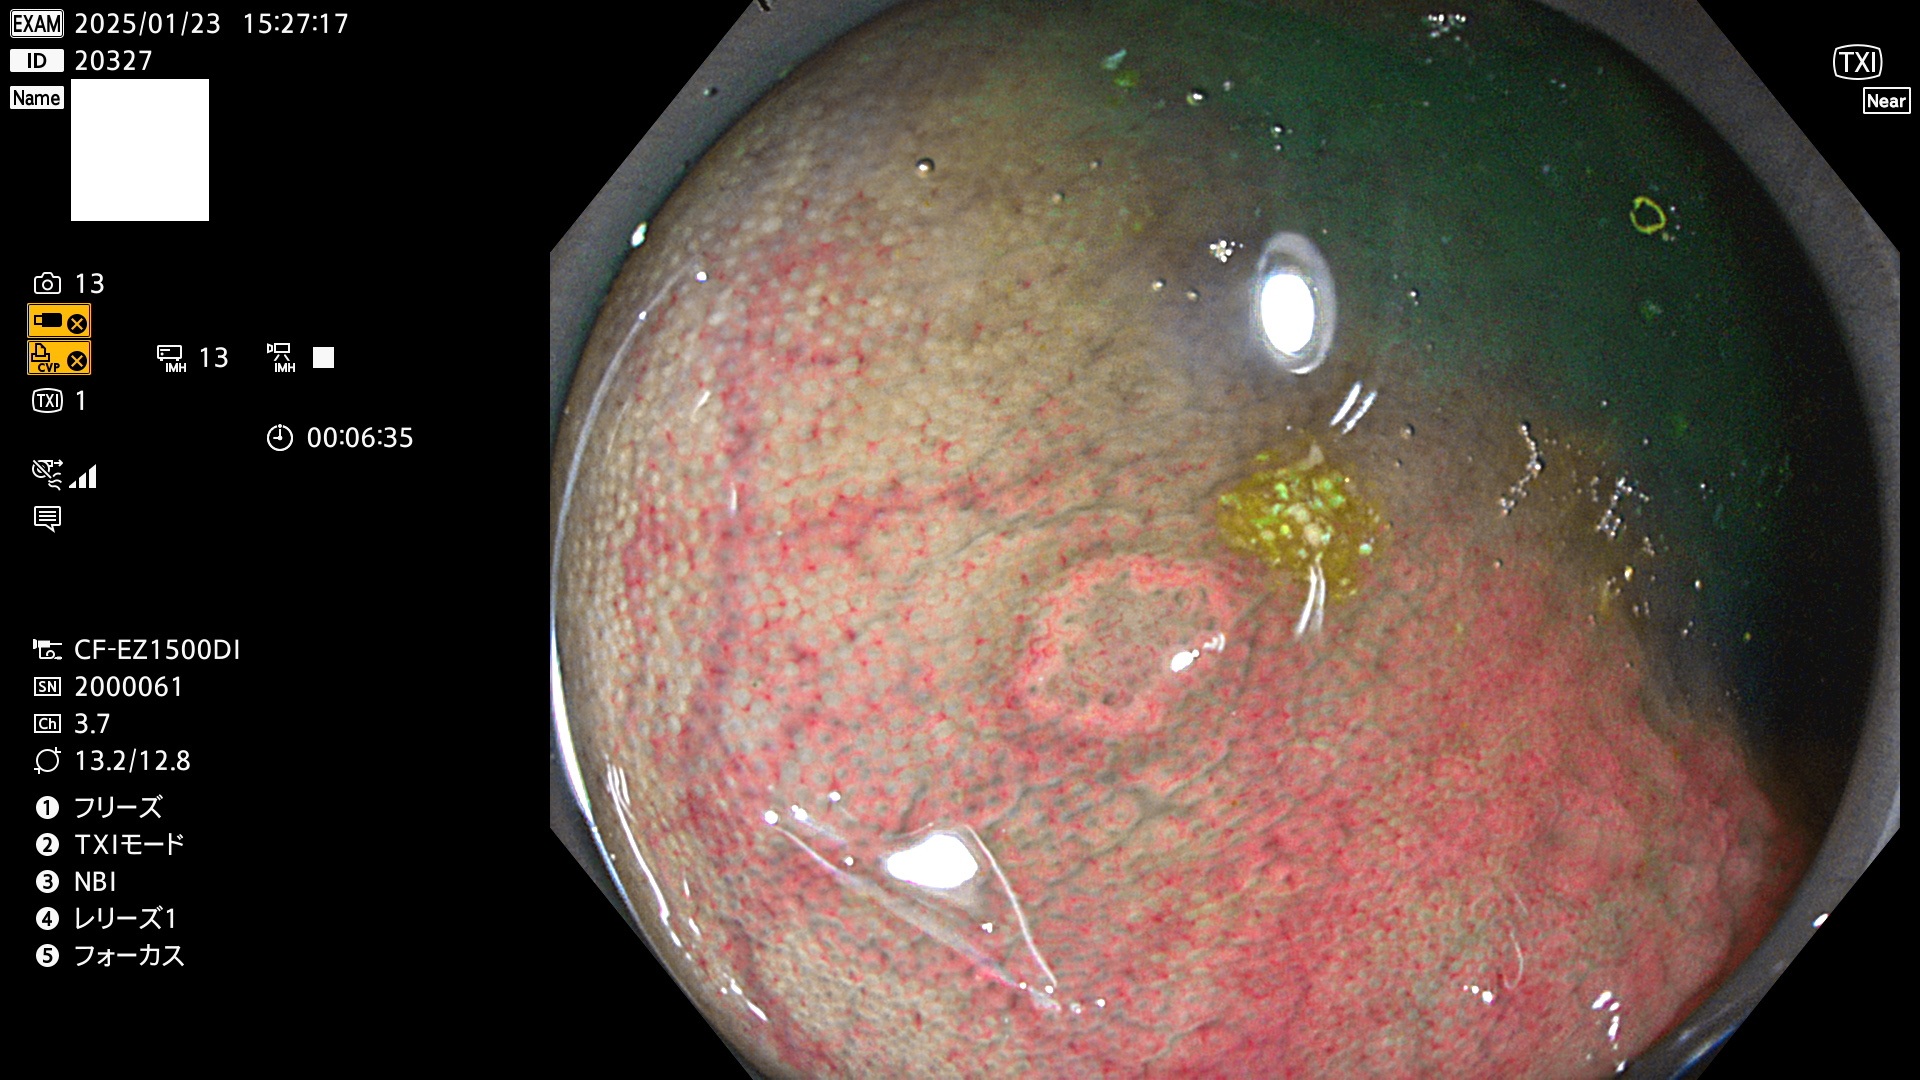

今週のUb、Uc型腺腫

完全に平坦な物をUb、陥凹している物をUcと呼びます。最も発見が難しく危険な病変です。

毎週の検査(木・金・土・日)に発見されたUb、Uc型・腺腫を、その週の日曜の夜にUPし1週間、提示します。

抽出の対象期間 2025年1月23日〜1月26日の4日間(45件の検査)3個 (3/45=6%)